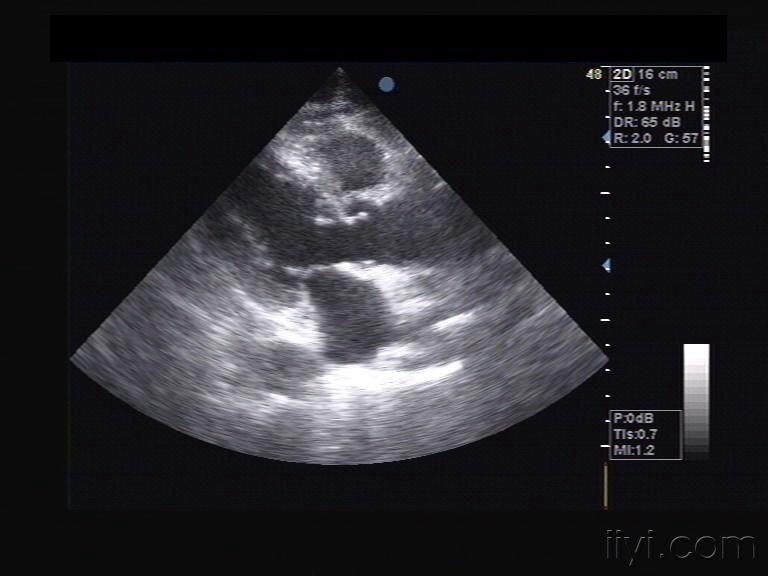

右位心超声报告模板

右位心超声报告模板,右位心超声描述报告

镜像右位心,永存右上腔静脉

右位心超声描述报告

右位心超声

右位心的超声模板

镜面右位心

镜面右位心的超声模板